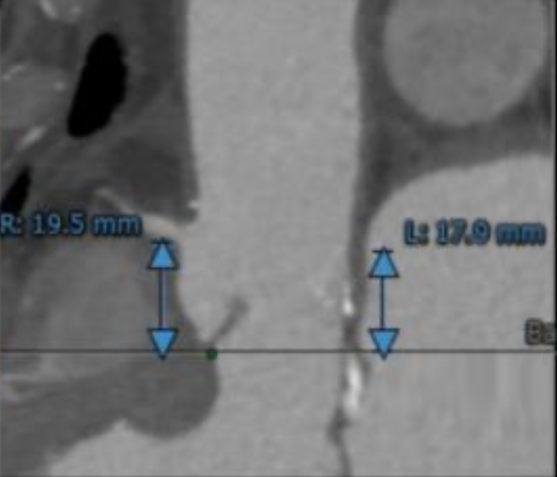

左冠开口高度17.9mm,右冠高度19.5mm,冠状动脉散在钙化。